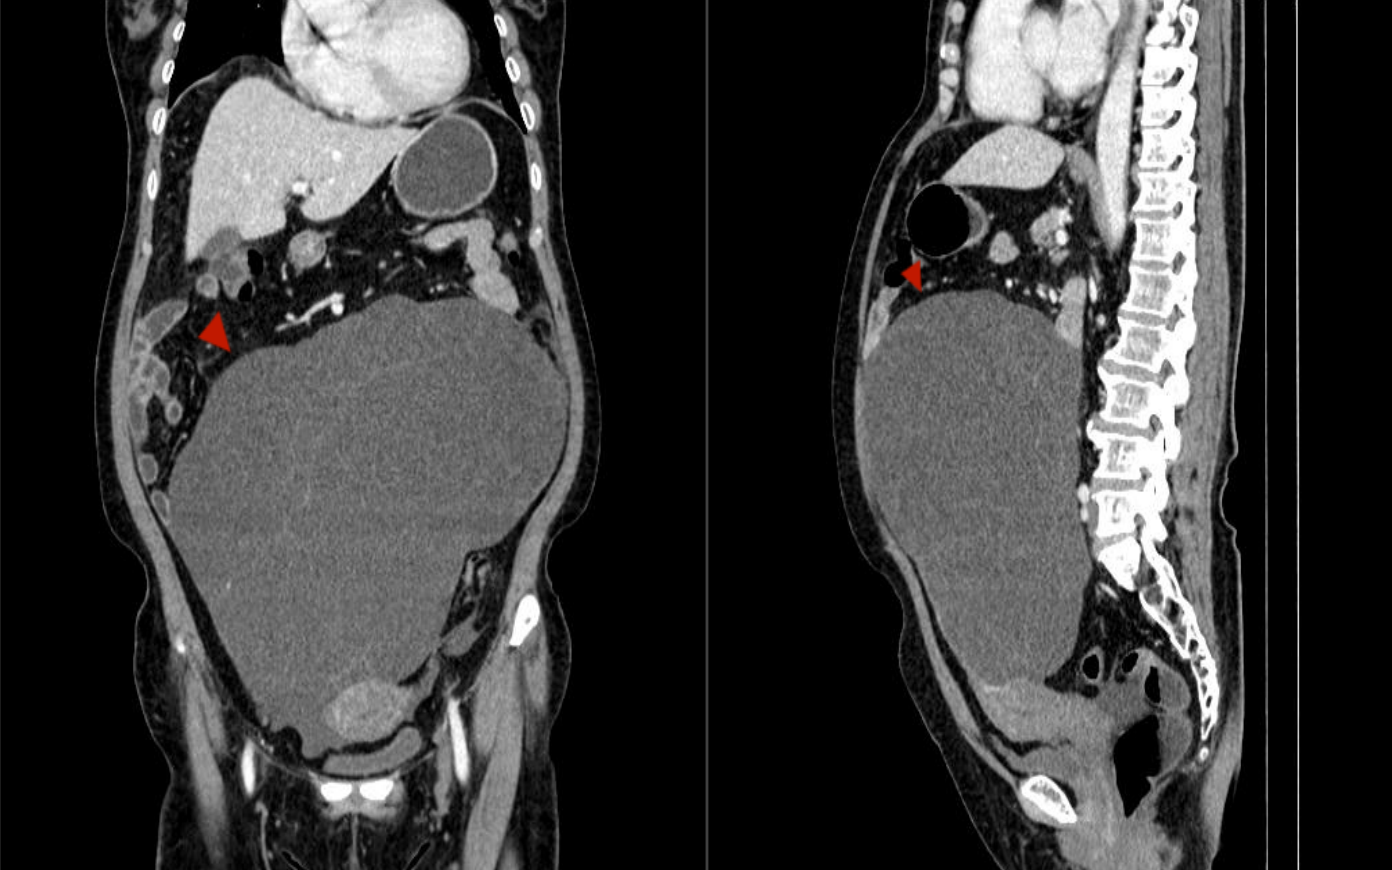

在我院妇产儿保医学中心(金山院区),医生经过详细的检查,发现林阿姨的盆腹腔里长了一个巨大的包块!

直径接近40厘米!几乎填满了整个盆腹腔,压迫着周围的器官。